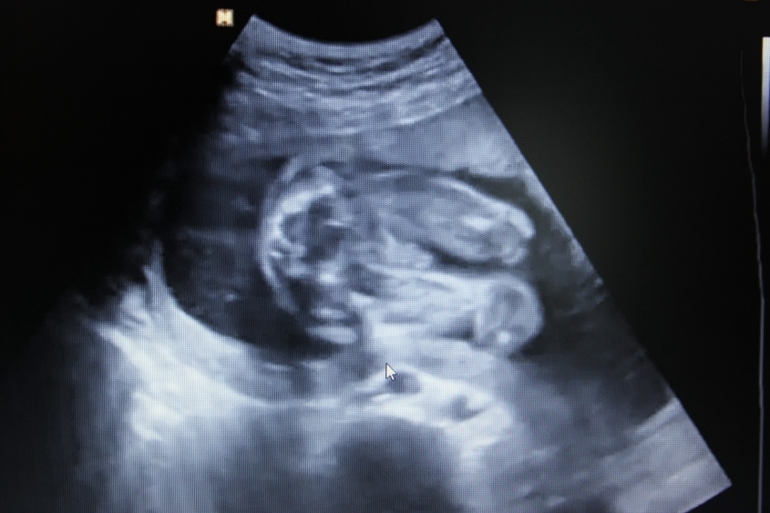

Попка и ножки: